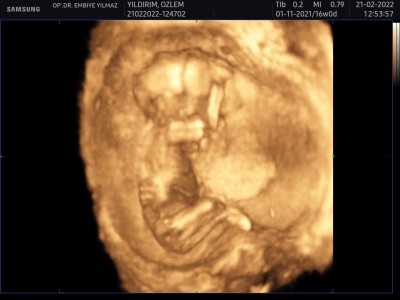

bu bacak bacak ustune atmis bebisim orda gorunen sey erkek organi olabilirmi acaba

Gebelik haftası 16

Özel bölgesini kapatmış canım. Bacak arası gözükmüyor

Yok canım değil bence bacaklarının arasında kalmış organı

Dediginiz yeri anladım da bilemiyorum herşey olabilir. Doktor görse söylerdi zaten söylemedi sanırım

ya boyle durdugu icin erkek olabilir ama net goremedim acmadi dedi o soyledi ama tabi sadece ihtimal

Ben de 17.haftada aynı böyle duruyordu hastanede biraz dolaştım biseyler yedim sonra tekrar baktirdim keşke  sizde öyle yapsaydınız veya kontrol süreniz varsa tekrar gidin pozisyonu müsait olur belki net söyler o zaman

Postun kapandığı için bjrdan yazıyorum sanki bende gördüm pipi değilde sanki topların olduğu kısım gibi :)

ayn doktorda oyle dedi bacaklarini kapamis ama onlar firlamis gibi ama yinede tam gormek lazim tabi